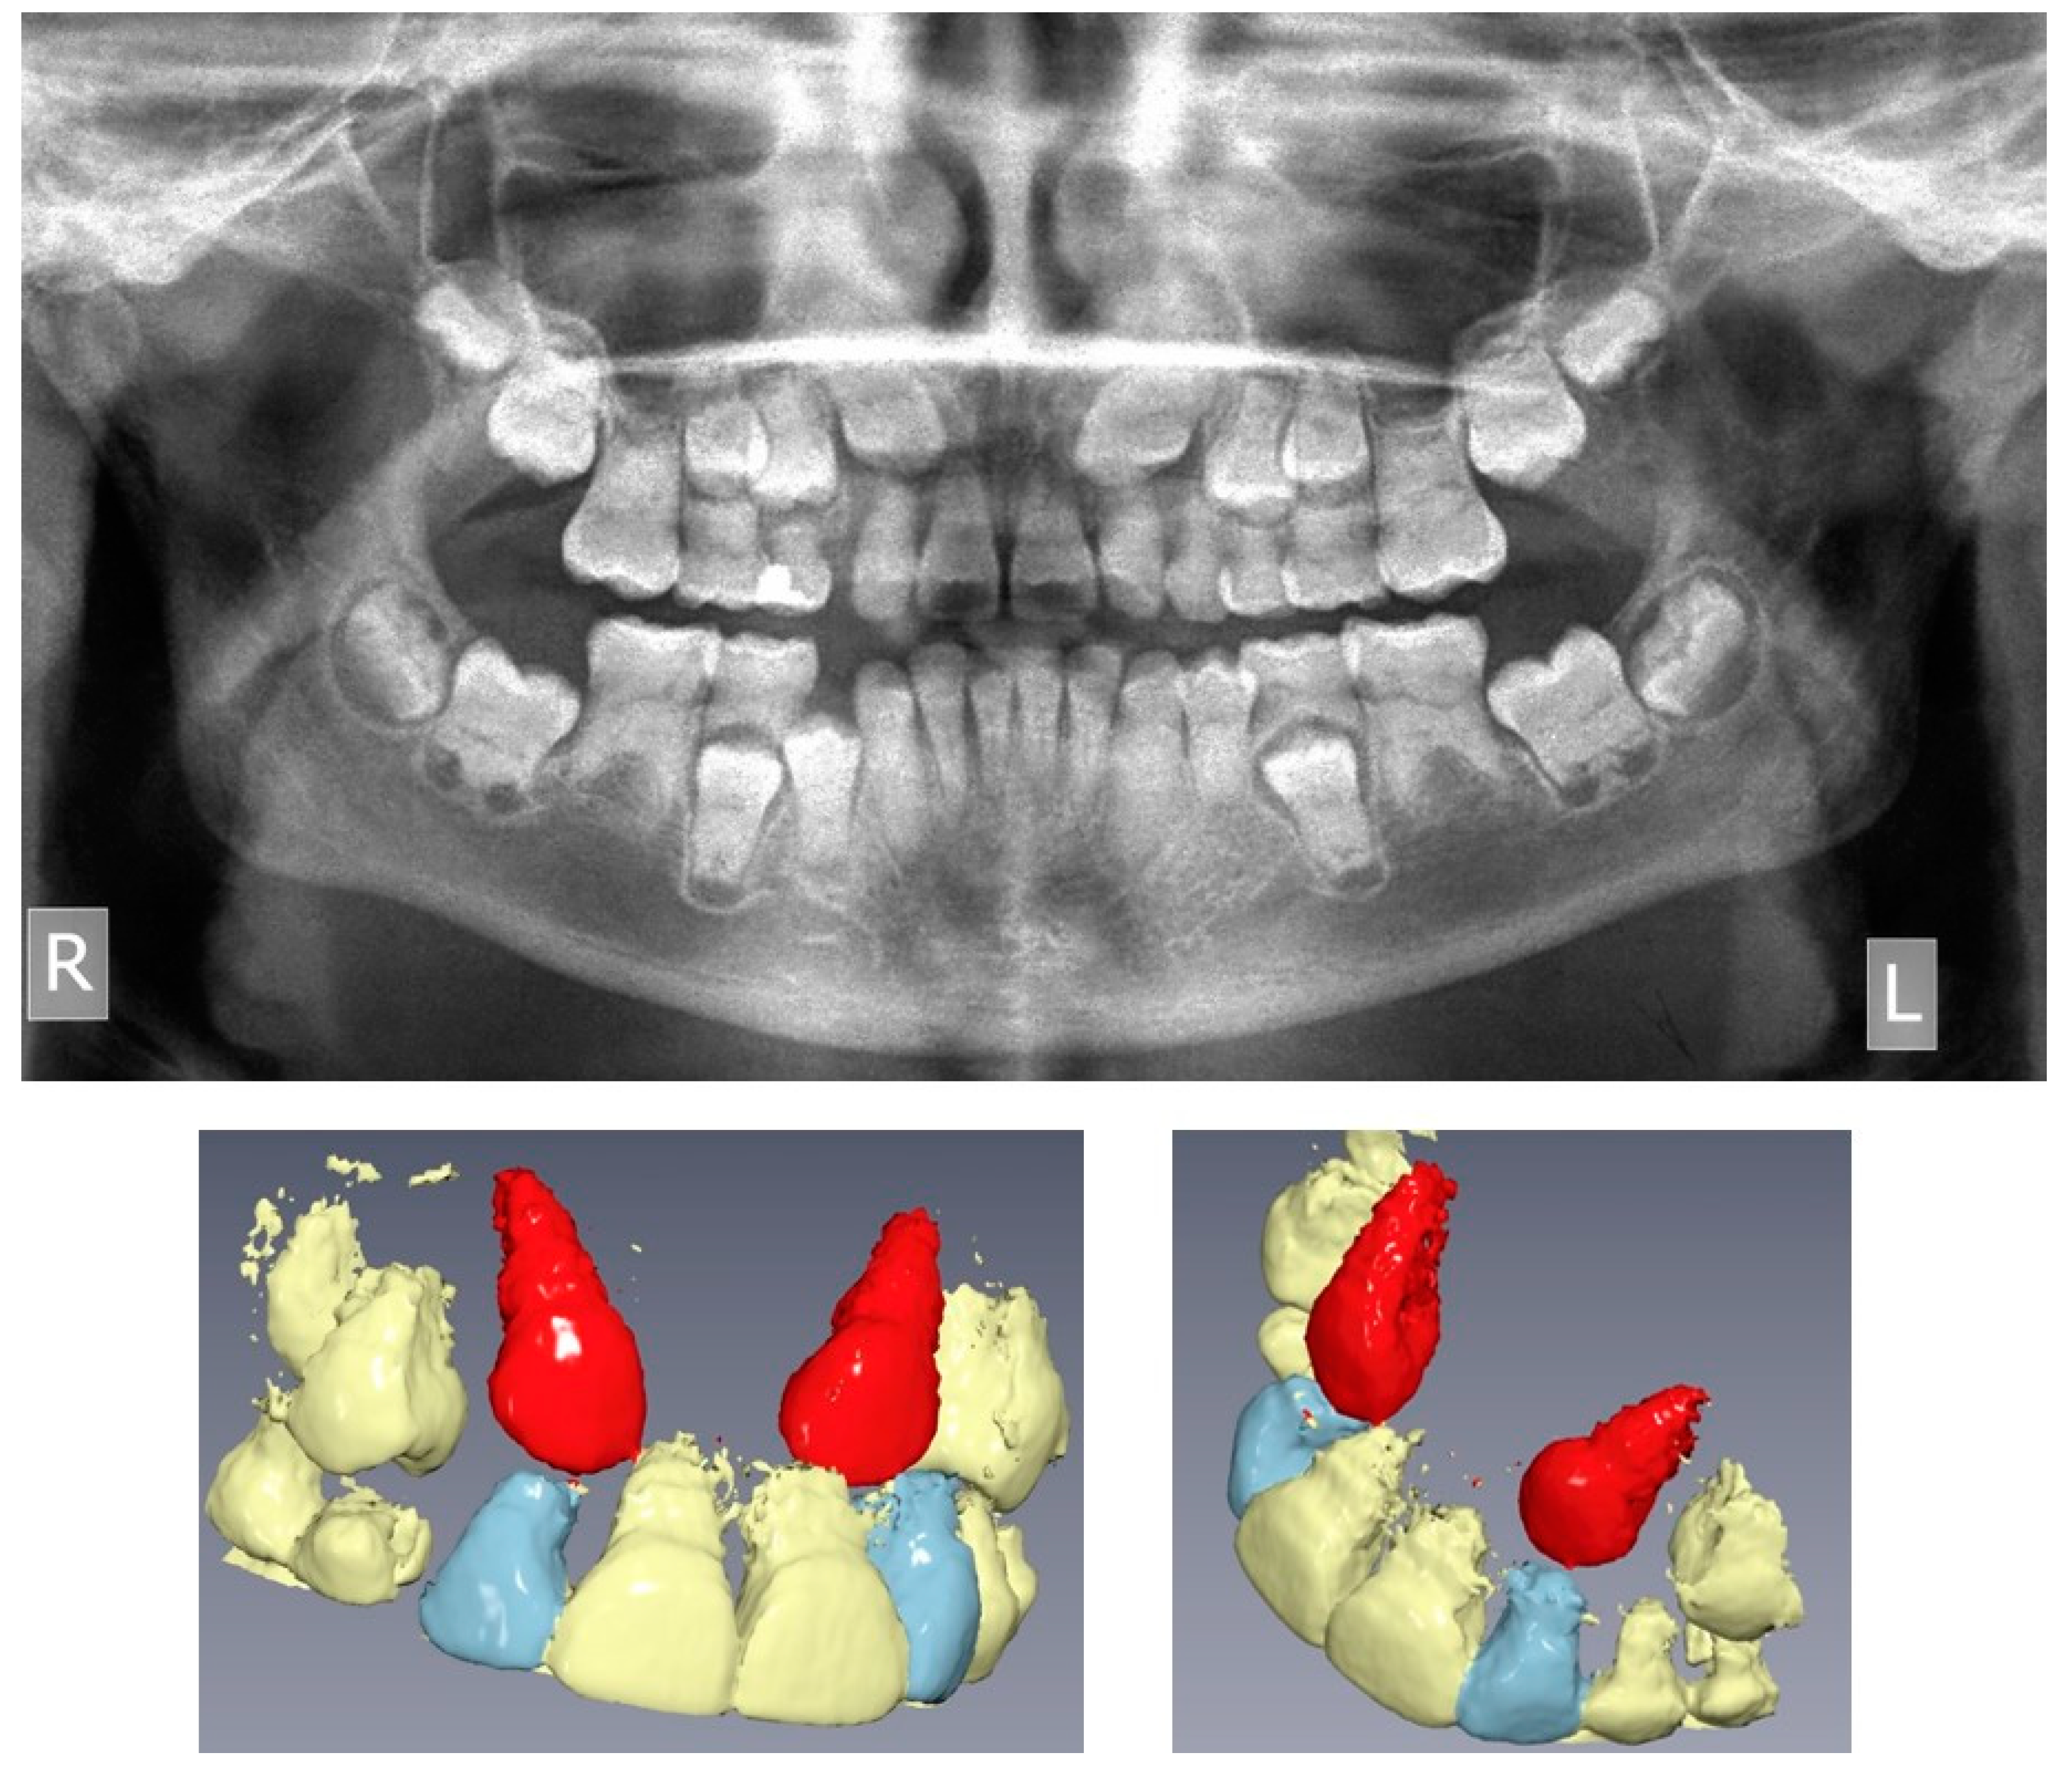

Figure 2.

Pre-treatment panoramic radiograph and Cone Beam Computed Tomography 3D reconstruction of the maxilla, showing the impacted upper canines (R: right, L: left, upper canines displayed in red).

The pre-treatment panoramic radiograph revealed short root length of most of the teeth, delayed tooth eruption, obliteration of pulp chambers and periapical radio-lucencies, not associated with periodontal disease or pulp inflammation. Horizontal crescent-shaped lines along the cementoenamel junction were evident in several teeth. Based on radiographic characteristics, this patient was subclassified as DD-Ic [10]. The permanent maxillary canines were impacted (Figure 1). Pre-treatment cone-beam-computed-tomography scans showed that the upper right maxillary canine (#13) was labially impacted; the contralateral canine (#23) displayed a more palatal position. Both teeth were above the roots of the adjacent lateral incisors, in close proximity to them and to the roots of the central incisors (Figure 2). Sclerosis of the maxilla and the mandible was absent in this case, as well as in the skeleton (Figure 3).